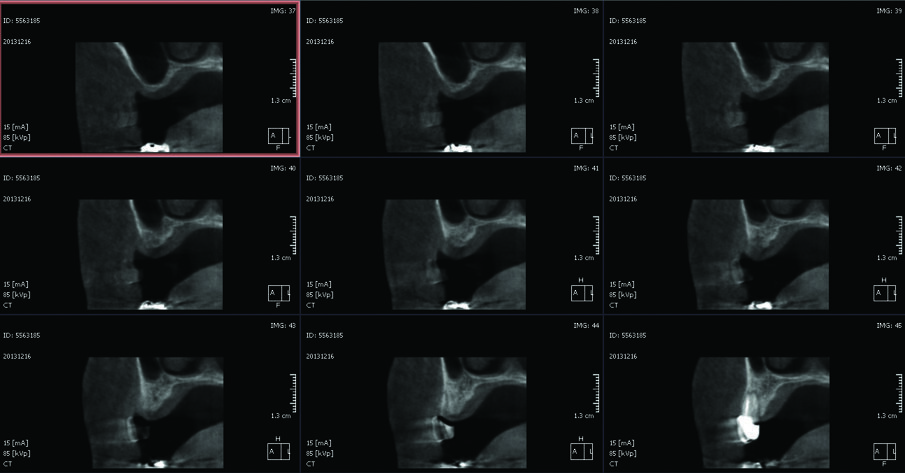

Paziente di sesso femminile, 48 anni, non fumatrice, si rivolge al nostro studio con la richiesta di ripristinare la normale masticazione, ostacolata dall’assenza di due denti precedentemente estratti. L’esame obiettivo evidenzia la mancanza di due elementi dentari nel primo quadrante (1.5 e 1.6). L’anamnesi della paziente è negativa, con un buon livello di igiene e un biotipo gengivale spesso. Viene pertanto prescritta una tomografia computerizzata, CBCT, per valutare il volume di osso disponibile per la riabilitazione (Fig. 1). Analizzando i risultati della CBCT si evince che l’osso basale non è sufficiente a stabilizzare gli impianti necessari per la riabilitazione implanto-protesica e appare ovvia l’esigenza di un aumento dei volumi dello stesso.

Fig. 1_CBCT preoperatoria: si noti la mancanza di osso necessario a stabilizzare due impianti.